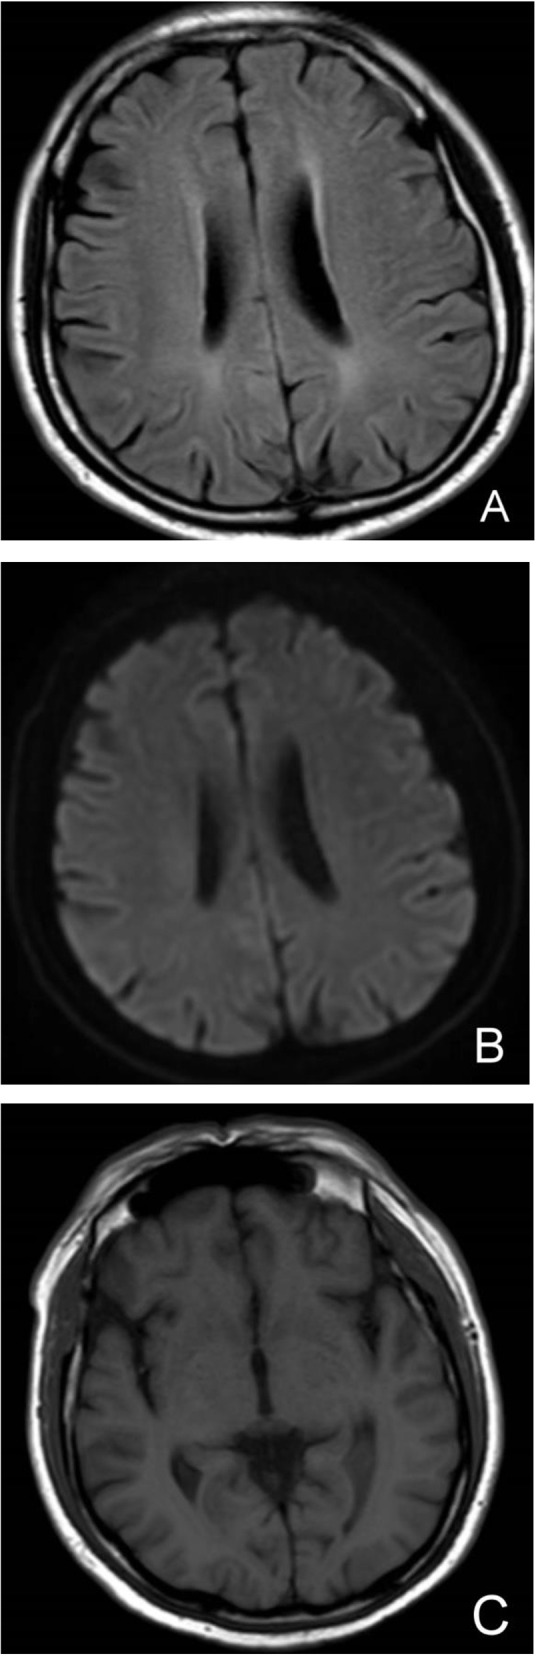

Sudden onset of unconsciousness on the 3rd day of admission, and cranial magnetic resonance imaging (MRI) of the brain showed: 1. ventral diffusion-weighted imaging (DWI) punctate high signal in the pontine brain; 2. bilateral frontal lobes with a little lacunar cerebral infarction; 3. mild demyelination changes in the white matter of the brain around the ventricles bilaterally; 4. mild septal sinusitis; 5. right vertebral artery terminal stenosis, right posterior cerebral artery P3 segment, anterior cerebral artery local mild stenosis, cerebrovascular atherosclerotic changes (Figure 3). We considered excluding the possibility of cerebral hemorrhage and cerebral infarction. And no meningeal enhancement changes were seen. The patient had a recurrent elevated temperature and was unconscious. We, therefore, concluded that lupus encephalopathy could not be ruled out and added methylprednisolone 40 mg/d. The symptoms did not improve significantly and there were still recurrent fevers and occasional headaches.

Figure 3.

(A): FLAIR sequence of head MRI; (B): DWI sequence of head MRI; (C): T1 sequence of head MRI. Head MRI did not show meningeal enhancement.